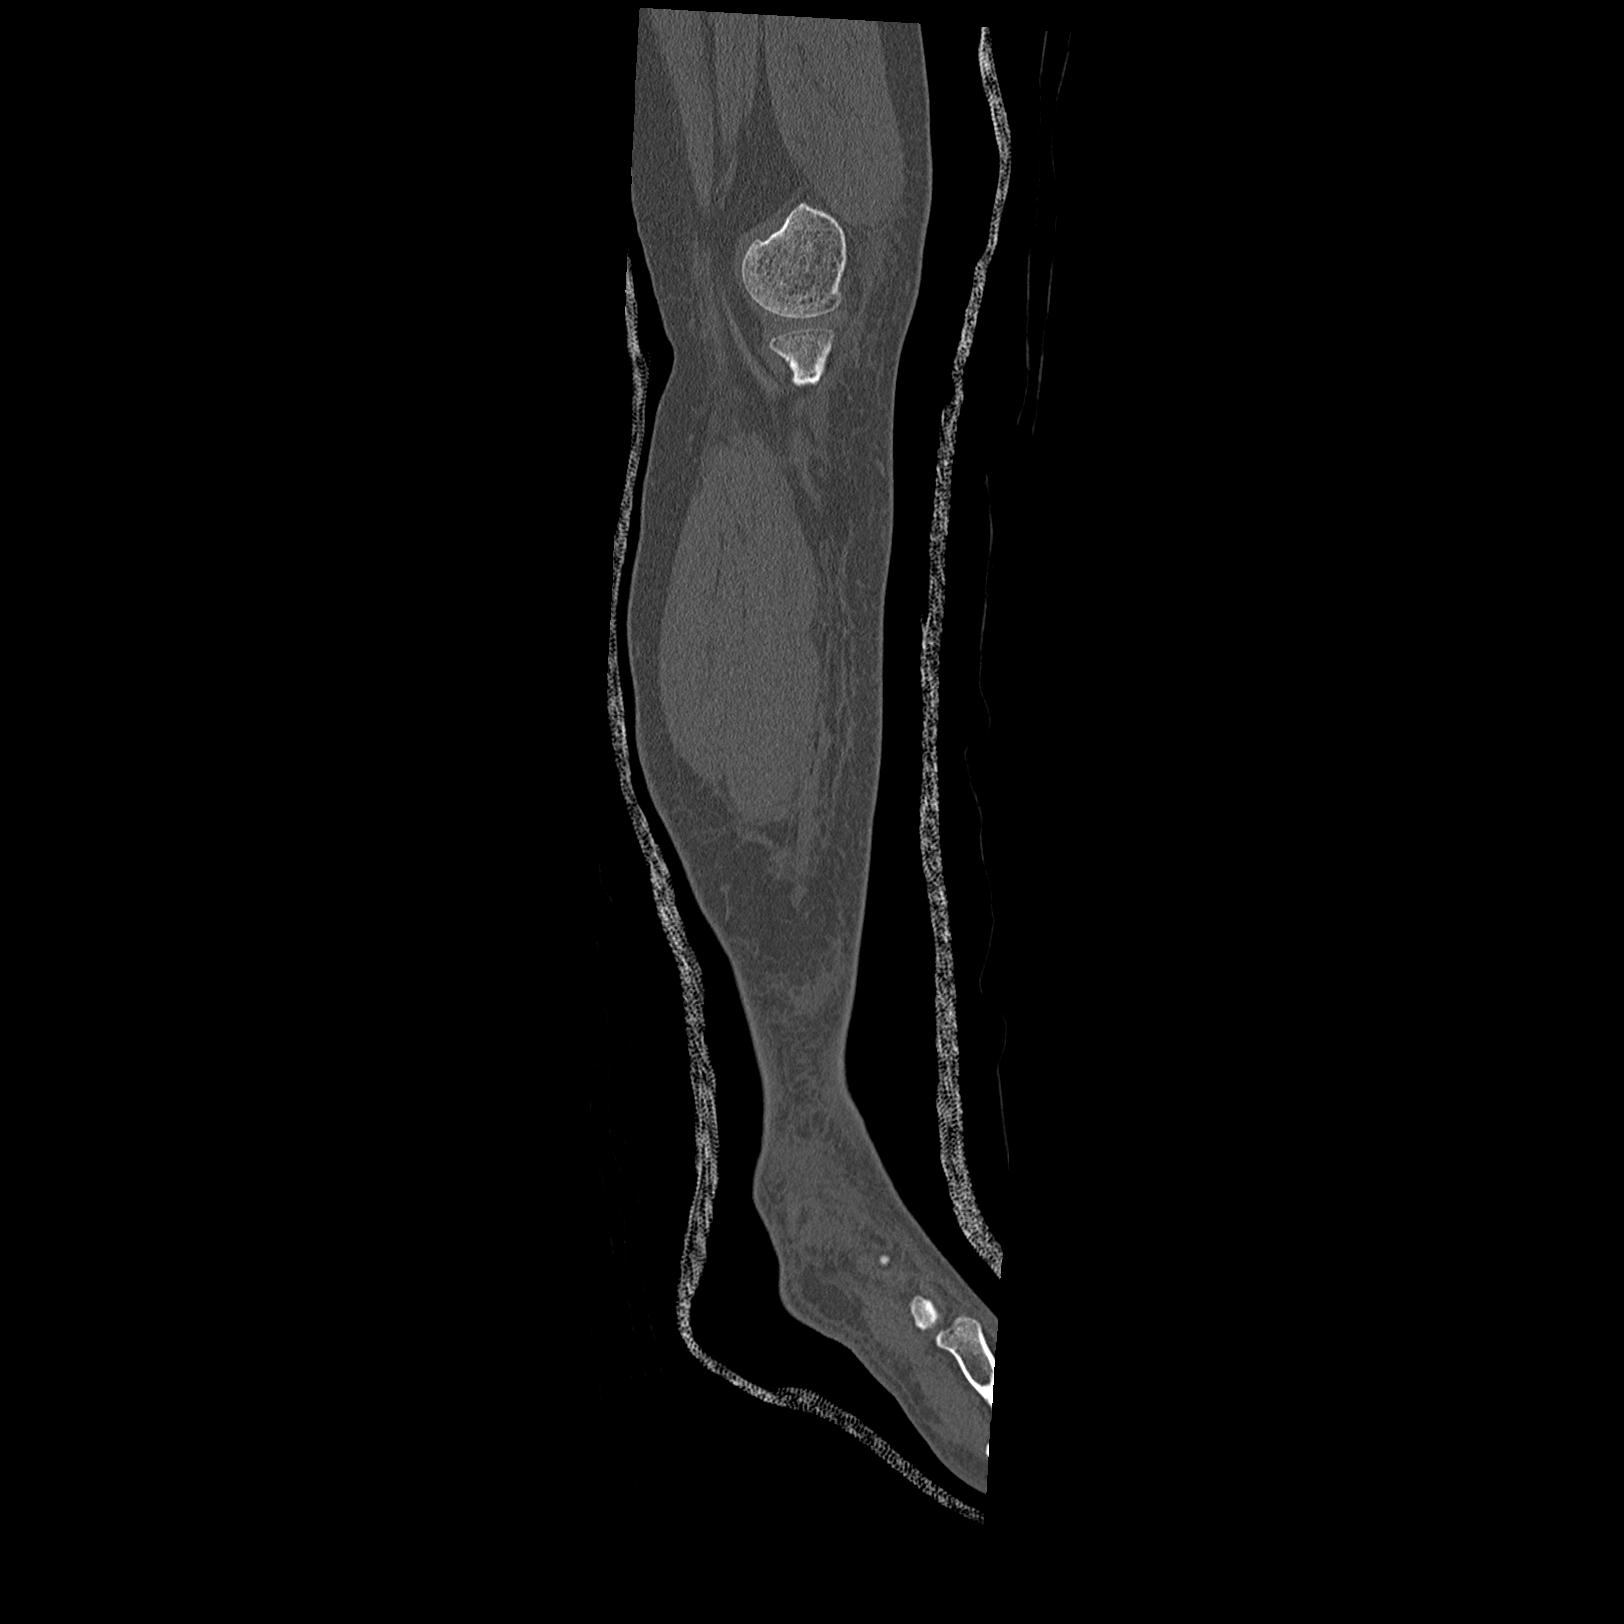

56476 8/28 4R 1/21 2R 左足関節 デジカメ写真 72歳女性 右足関節AS

102755 1/4 2R 1/15 2R 右足関節 68歳女性 右三果脱臼骨折